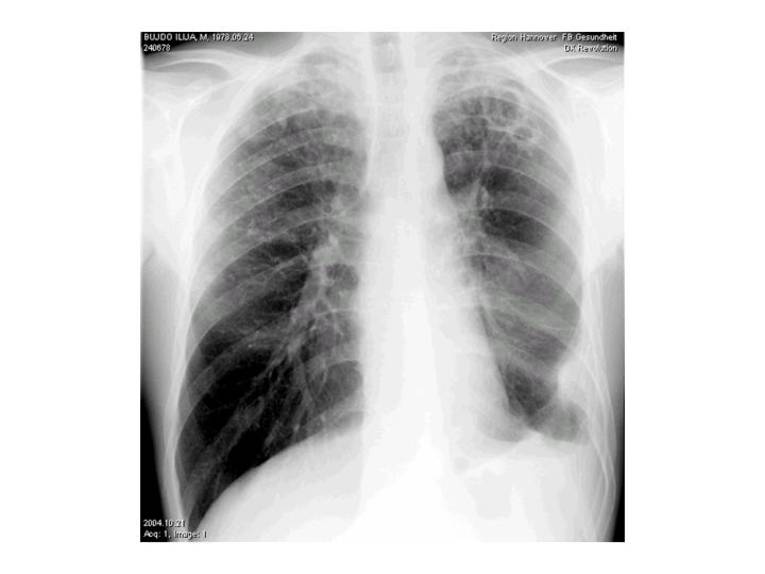

Tuberkulose im Bild

Zu Beginn der Krankheit gibt es häufig keine typischen Krankheitszeichen.

Menschen, die an Lungentuberkulose erkrankt sind, haben oft Husten und leichtes Fieber. Diese Beschwerden sind jedoch nicht spezifisch und treten beispielsweise auch bei Erkältungen auf. Halten die Symptome jedoch über mehrere Wochen an oder treten weitere Beschwerden wie starkes Schwitzen, ungewollter Gewichtsverlust oder Müdigkeit hinzu, muss auch an Tuberkulose gedacht werden. Dann ist es erforderlich, eine Röntgenaufnahme der Lunge und eventuell weitere Untersuchungen zu veranlassen. In selteneren Fällen kann Tuberkulose auch andere Organe als die Lunge befallen. Insbesondere, wenn man Kontakt zu jemandem mit Tuberkulose hatte, sollte man mit diesen Beschwerden einen Arzt aufzusuchen.